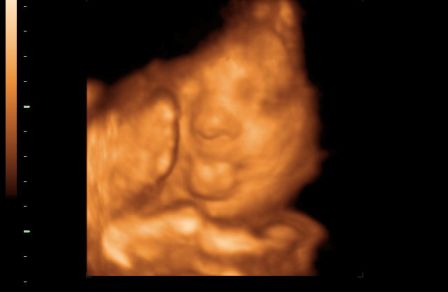

A másik, ma voltunk a 30 hetes UH-on és 4D-n.

Baba jól van, feje lent, lepényem elvándorolt, így már nem állja el a baba útját. Viszont meszesedik a lepényem, aminek még nagyon nem kéne, azt mondták, ez lehet a cukor miatt...

Ezzel valakinek tapasztalata???

Úgyhogy nem azt mondták, hogy várnak szeretettel a 38. héten, hanem korábban rá kell nézni...

Kissrác nem mutatta meg magát, az egyik oldalát az arcának befúrta a lepénybe, a másikat eltakarta a kezeivel.

Végig le volt árnyékolva, alig készült kép, az is féloldalas.

Fél órát bökdöste a szonográfus, de nem mozdult, hanem kinyújtotta a nyelvét, aztán kiröhögött minket, na szép! :)

1550 gr, és a méretei alapján pár nappal előbb kéne születnie, ami a doki miatt jó lenne. Szerintetek ha tovább meszesedik a méhlepény, megindítják korábban...?

És a képek:

Kép Kinyújtja a nyelvét... Kép Aztán kiröhög... Kép És kb ilyen képek lettek :(